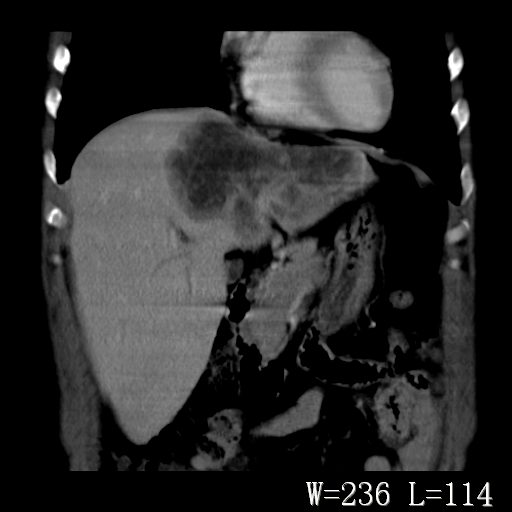

标题: CT27340:肝脏病变?

男,45岁,发热、乏力半月,午后为主。

对比剂快进快出,首先考虑肝左叶巨块型肝癌。

其次,感染性病变,如肝脓疡不排除。

蜂巢,肝脓肿

蜂巢状,支持!肝脓肿的诊断。